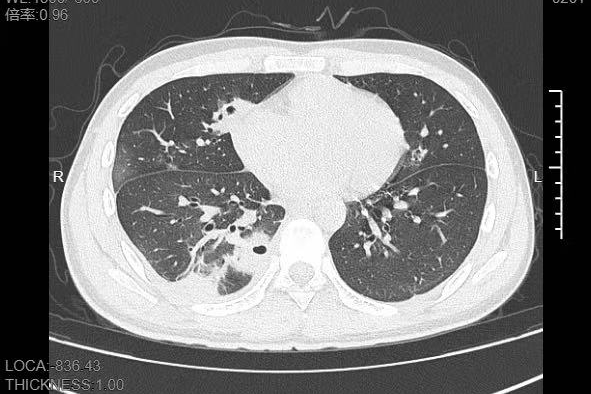

接诊的呼吸与危重症医学科丁群力主任医师一看他的症状,立刻安排了CT检查,结果显示:小林的肺里有十几个空洞,部分肺组织已经坏死,这是典型的血源性肺脓肿。